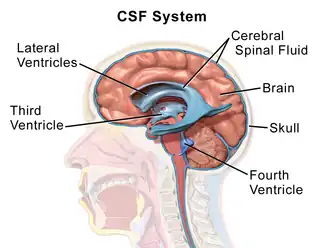

The blood-brain barrier protects the brain by restricting the ability of large molecules to cross the barrier between the blood, CSF, and interstitial fluid of the brain. ICV injection circumvents this barrier, to be able to deliver drugs to the CSF. An ICV device is implanted under the scalp, into the subgaleal space where it is then connected to the ventricles with an outlet catheter. This allows for repeated doses of the drug without having to re-puncture the scalp.[14]

Production of CSF is at a rate of about .3 mL/minute and occurs at the ependymal and parenchymal regions and the choroid plexus. Up to 80 percent of CSF production comes from the choroid plexus, which is present within the lateral, third, and fourth ventricles. The choroid is lined with epithelium with tight junctions at the ventricular side of the cells. This comprises the blood-CSF barrier. Whereas the blood-brain barrier is made up of vascular endothelium in capillary beds throughout the CNS parenchyma.[13]